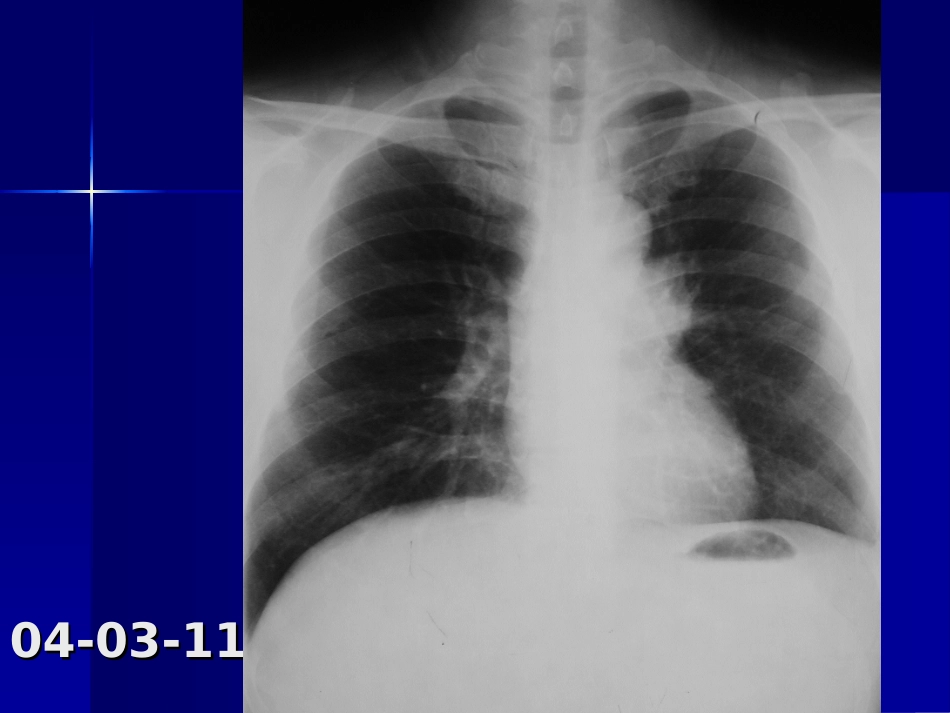

病例一病例一男,男,5252岁,体检发现前纵岁,体检发现前纵隔肿物隔肿物2020余天,胸闷、无余天,胸闷、无力,低烧十余天,抗炎治力,低烧十余天,抗炎治疗后好转。疗后好转。04-03-1104-03-11病理结果:右肺上叶尖段病理结果:右肺上叶尖段及纵隔慢性肉芽肿性炎症,及纵隔慢性肉芽肿性炎症,考虑结核。考虑结核。病例二病例二男,男,5454岁,咳嗽胸闷一年岁,咳嗽胸闷一年半,咳血半,咳血2020余天。余天。04-02-2704-02-2704-02-2604-02-26病理结果:病理结果:右肺下叶内基底段炎性假瘤右肺下叶内基底段炎性假瘤病例三病例三男,42岁,咳嗽一月余,无发热,咳血04-03-0504-03-05抗炎治疗一周后,病灶明抗炎治疗一周后,病灶明显缩小变淡。显缩小变淡。诊断:右肺下叶球性肺炎诊断:右肺下叶球性肺炎病例三病例三男,男,4646岁,岁,02-11-0402-11-0402-11-02-11-0404病理结果:管状—绒毛状病理结果:管状—绒毛状腺瘤腺瘤病例四病例四男,男,3434岁,发现腹部肿岁,发现腹部肿物一月。物一月。04-02-1804-02-1804-02-2604-02-26病理结果:肝左叶肝癌病理结果:肝左叶肝癌